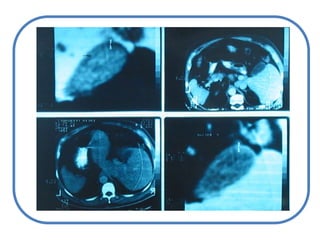

Estudio del pacienteictéricoCLÍNICOINTERROGATORIO

Sindrome icterico